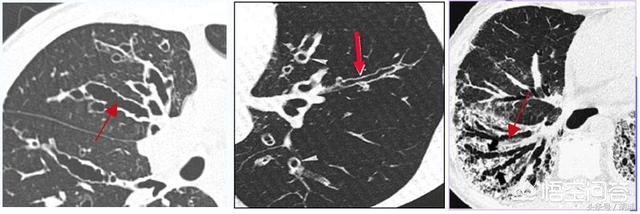

哪些疾病会导致支气管扩张

中国是结核大国,患结核病的人口甚至超过了欧洲一些国家的总人口,而结核病恰恰是支气管扩张的一个重要原因,很多人结核痊愈后仍然咳嗽不止,甚至出现咯血就是遗留的支气管扩张造成的,另外,各种肺炎不管是细菌性的,病毒性的还是真菌性肺炎,都有可能在感染控制痊愈后遗留支气管扩张的毛病,还有一些遗传性疾病,比如纤毛不动综合征很重要的表现就是支气管扩张和顽固性的肺部感染,其主要发病原因就是全身带纤毛的结构和细胞没有活力,气管纤毛没活力粘液排不出就总是感染,感染久了就支气管扩张,精子的尾巴没有活力就不育。女性还有一个容易发生的支气管扩张成为中叶综合征,好发于右肺中叶,这个右中叶支气管管腔窄,根部周围有较多淋巴结包绕,在感染时很容易肿大压迫支气管导致其中的分泌物不能排除,久而久之就演变成支气管扩张和肺不张。